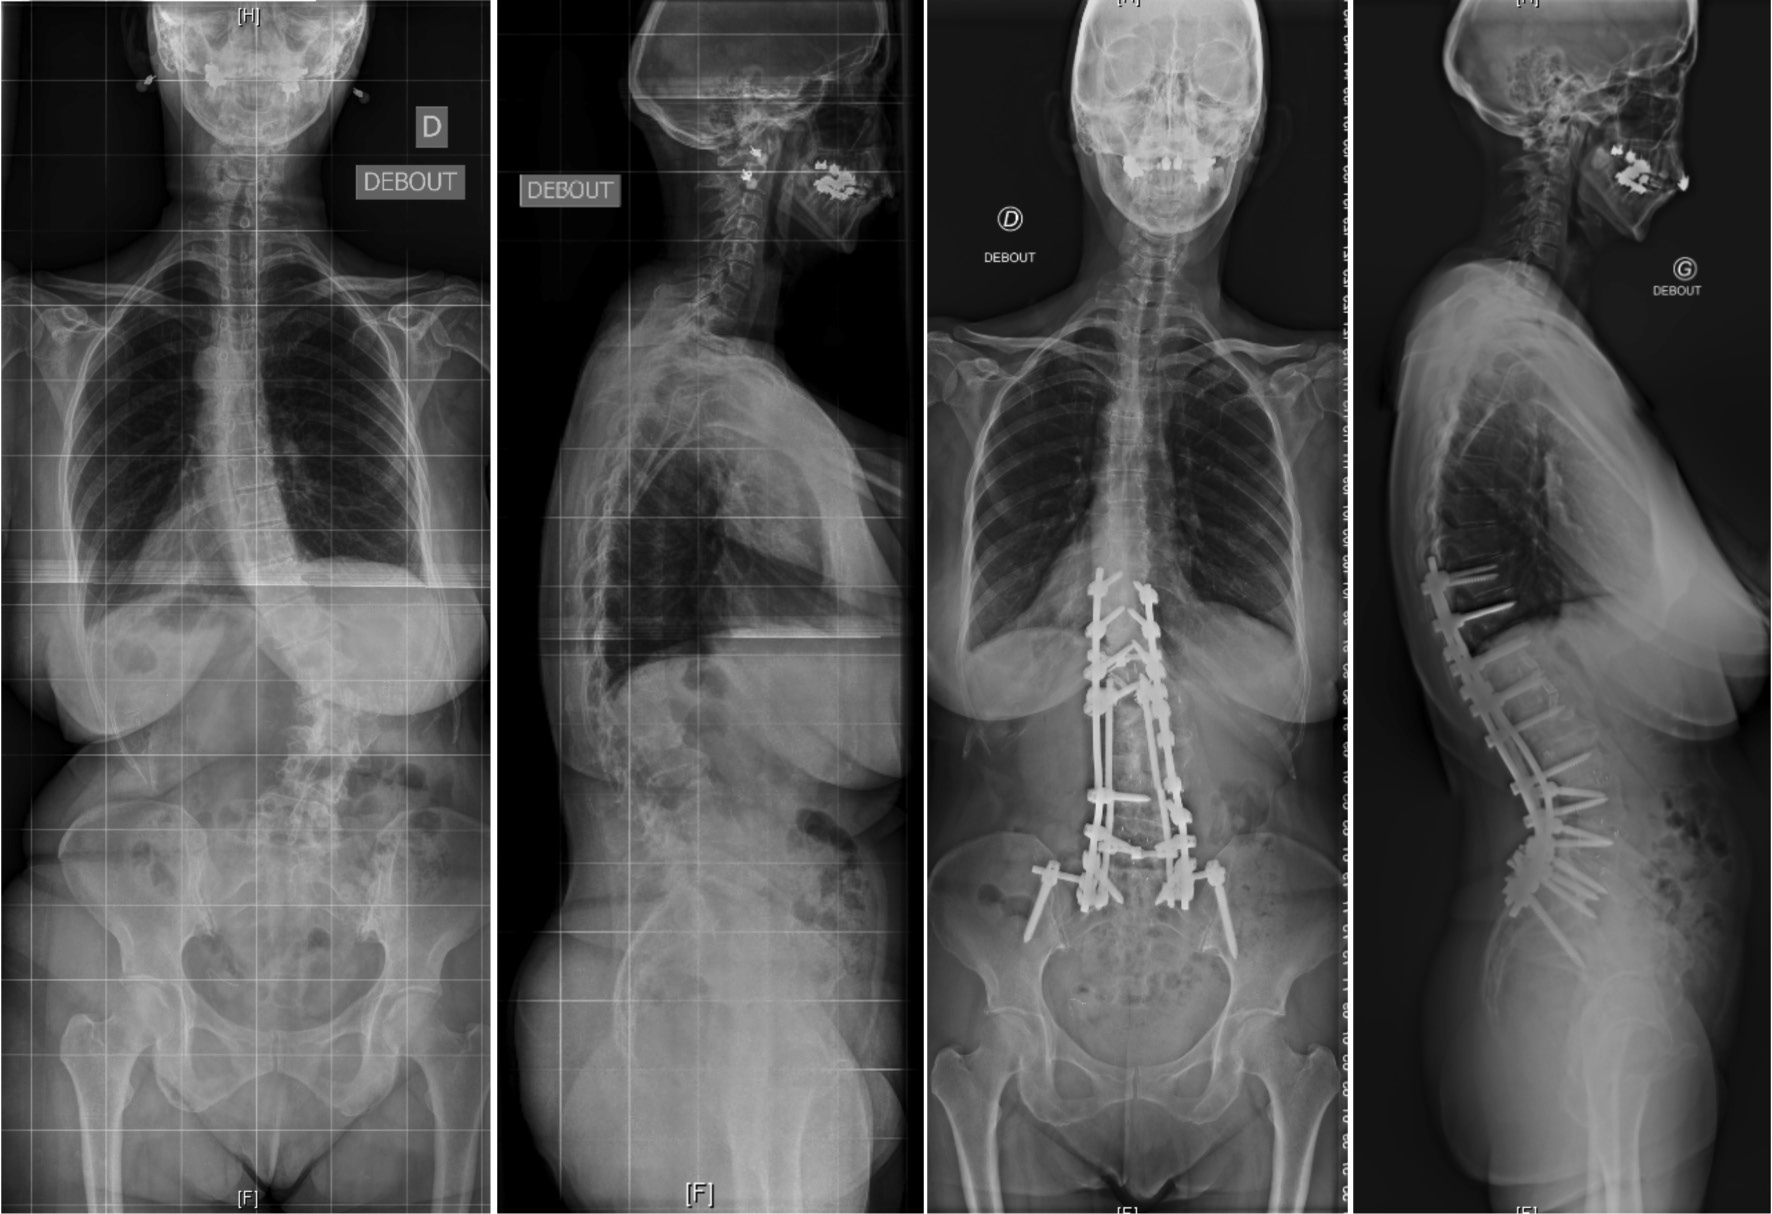

脊柱形态与症状来源

成人脊柱侧凸通常与腰椎前凸的丢失与胸腰交界处的后凸畸形有关,从而导致躯干前倾造成失平衡,此时人体往往会通过骨盆的后倾和膝关节的屈曲进行代偿。不断进展矢状面畸形最终会影响患者的健康相关的生活质量(HRQoL)。同时,由于椎旁肌的能量消耗增加以抵消身体前倾所造成的失平衡,从而导致腰背痛,肌肉劳损和活动功能障碍。

成人脊柱侧凸畸形与后凸畸形

在过去的十年中,微创MIS技术治疗ASD已取得了重大进展。微创手术方式通常是通过前路腹膜后入路椎间融合器植入与后路经皮内固定相结合实现手术减压、固定及融合的目标。这种手术方式更适用于轻度到中度的ASD患者,此类患者多表现为有限节段的腰椎退行性改变和较好的弯曲柔韧性。对于MIS手术,单或双节段的退变为MIS治疗的良好手术指征,此时进行早期干预能够防止弯曲进一步的发展。目前已存在较多的文献表明通过MIS技术能够有效地矫正腰椎畸形,并且可以改善腰背痛以及神经根性疼痛。 Phan等对MIS技术治疗ASD患者进行荟萃分析后提出MIS技术的远期融合率满意且并发症发生率相对较低。Kanter等在其对MIS技术治疗ADS患者的综述中表明MIS技术在带来满意疗效的同时能够降低围手术期并发症。但是因其矫形能力有限,不建议将其应用于严重畸形的病例。

当然,MIS的局限性仍然是存在的。ISSG国际脊柱研究学组认为MIS技术仍然存在所谓的“天花板效应”以下情况不建议微创手术PI-LL > 20°,SVA > 9.5 cm,PT > 30°。严重的矢状面与冠状面畸形与失衡,僵硬性畸形或椎间已出现融合应通过后路开放手术解决。Mummaneni等将这一流程进行了细化,综合症状来源、冠状面和矢状面曲度、椎间盘退变程度因素将ADS分为6级。认定1-4级建议行微创手术,5-6级建议开放手术治疗。ISSG国际脊柱研究学组也曾提出基于影像特点的ADS患者手术方式的选择流程,并在2019年出版了最新修订的手术方式选择流程图。